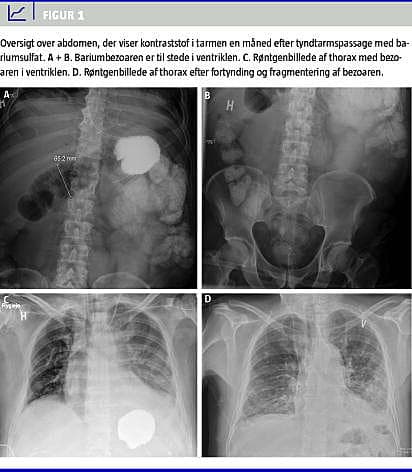

Der blev lavet en oversigt over abdomen, hvor man så en bariumbezoar i ventriklen. Denne havde været til stede, siden der blev foretaget tyndtarmspassage (Figur 1 ). Der blev lavet en gastroskopi, hvor bezoaren ved hjælp af vand og sodavand blev fragmenteret, fortyndet og aspireret. Herefter ophørte patientens gastrointestinale symptomer. Han blev udskrevet i velbefindende to måneder efter det første kirurgiske indgreb.

I begyndelsen havde patienten kun intermitterende symptomer på okklusion, men efterhånden blev de mere vedvarende. Bariumbezoaren var til stede og blev beskrevet på alle røntgenundersøgelser, der blev udført efter tyndtarmspassagen. Bezoaren har formentlig været mobil og har derved forårsaget en symptomgivende, intermitterende aflukning af anastomosen for til sidst at aflukke permanent for gastroenteroanastomosen.